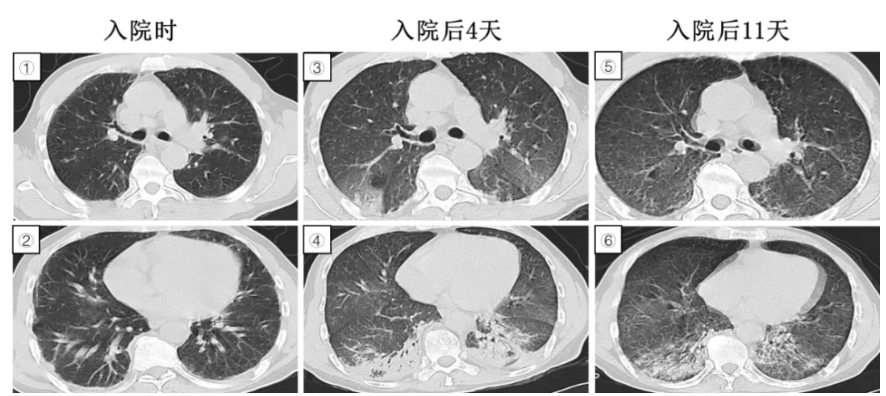

图3:①-⑥CT图像提示大叶性肺实变,空气充气征明显,抗感染治疗无效,胸膜下实变影增多,糖皮质激素治疗1个月后明显消散。

这位患者1月前受凉后出现咳嗽、白粘痰,无发热,血常规提示白细胞9*109/L,中性粒细胞百分比76.6%,血CRP117mg/L,外院CT提示左下肺大叶性肺炎改变,予以哌拉西林/他唑巴坦联合左氧氟沙星静滴抗感染1周无改善,复查CT提示左下肺炎较前进展,右肺新发实变影,出现发热1天,转来我科进一步诊治,气管镜检查灌洗液NGS阴性,肺穿刺活检病理提示肺组织慢性炎症,伴间质纤维组织增生。

治疗经过:予以甲强龙40mg静滴qd,后改为口服甲泼尼松片24mgqd,1月后复查胸部CT提示肺炎明显吸收好转,逐渐减量维持6个月疗程停药。

疾病要点:隐源性机化性肺炎以前称为闭塞性细支气管炎伴机化性肺炎,肉芽组织阻塞细支气管和肺泡管,伴相邻肺泡的慢性炎症和机化性肺炎。肺部CT可见斑片状气腔实变(90%患者)、磨玻璃影、小结节影和支气管壁增厚扩张;斑片状影常分布于胸膜下,多位于下肺;反晕征(周围实变伴中央透亮区)较为罕见但对机化性肺炎具有相对特异性。需使用糖皮质激素治疗,复发率高达25%,因此治疗疗程通常持续6至12个月。